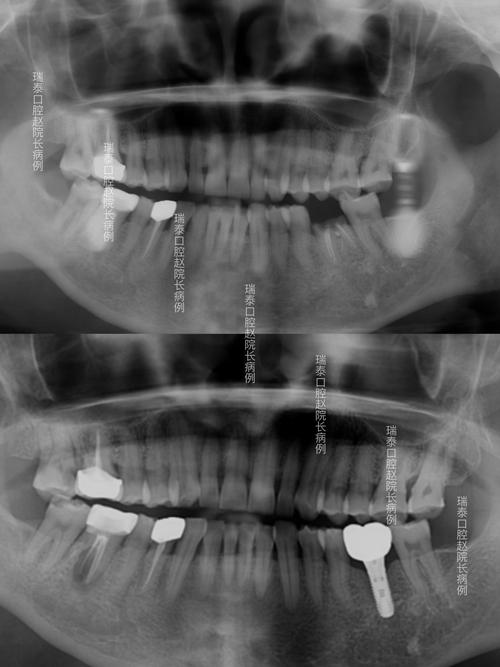

- 曲面断层片(全景片,OPG):可一次性显示全口牙齿、牙槽骨、颌骨、上颌窦、下颌神经管等结构,是种植牙前最常用的X光检查,通过曲面断层片,医生可初步判断缺牙区牙槽骨的总体高度、宽度,以及下颌神经管的走行位置(通常位于下颌骨内,距离牙槽嵴顶10-15mm)。

- 局限性:二维成像,存在影像重叠问题,牙槽骨的宽度在全景片上可能被放大或缩小,实际测量值存在误差;下颌神经管、上颌窦底的边界可能因重叠显示不清,无法精确判断种植体与这些结构的距离;对于骨量严重不足或复杂病例,全景片难以提供足够精细的三维数据。

当X光检查提示骨量不足、解剖结构复杂(如下颌神经管位置靠近牙槽嵴、上颌窦低垂)或需进行复杂种植(如全口种植、穿颧种植)时,CT检查(尤其是口腔专用锥形束CT,CBCT)是必不可少的一步。